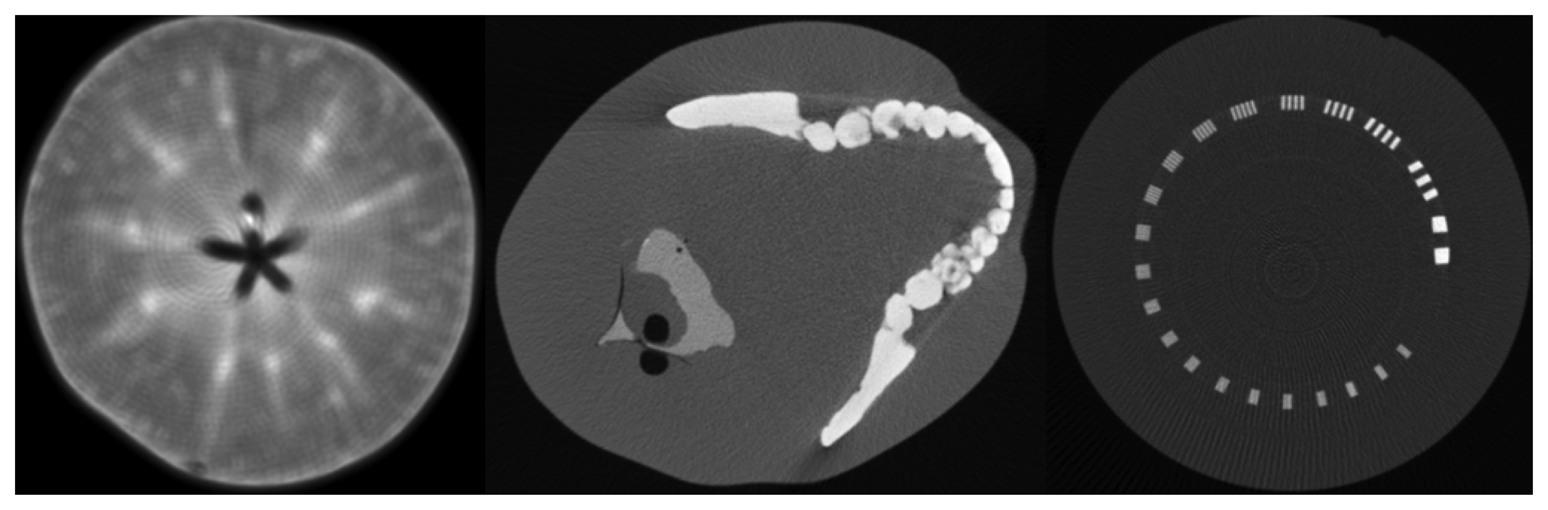

3.5. Reconstructed Images

In whole CT detector test environment, we scanned some phantoms, such as an apple, a head phantom and a line pair phantom. The reconstruction method is fan beam FBP algorithm, without data correction. The result is showed in Figure 11. The general inner parts of these phantoms are clearly showed in the image except for some detailed information. Since lack of uniformity correction, circle-like artifacts is rather obvious, especially in apple image and line-pair image. Stripe artifact is conspicuous in head phantom image. Further analysis of image quality is beyond the scope of this article, we will demonstrate more analysis and result in the future articles.